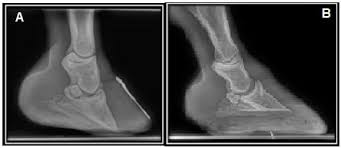

Anatomia básica do casco equino

O casco é composto por várias partes, incluindo a muralha, sola, ranilha e linha branca. Cada uma dessas estruturas tem funções específicas:

- Muralha: Parte externa que suporta a maior parte do peso.

- Sola: Superfície inferior que protege as estruturas internas.

- Ranilha: Estrutura em forma de "V" que auxilia na absorção de impactos.

- Linha branca: Área de junção entre a muralha e a sola.

A compreensão da anatomia do casco é fundamental para identificar e tratar problemas precocemente.

O casco funciona como um amortecedor natural, absorvendo os impactos durante a movimentação. Ele também distribui o peso do cavalo de maneira equilibrada, permitindo uma locomoção eficiente e confortável. Problemas no casco podem levar a alterações na marcha, claudicação e até mesmo lesões em outras partes do aparelho locomotor .